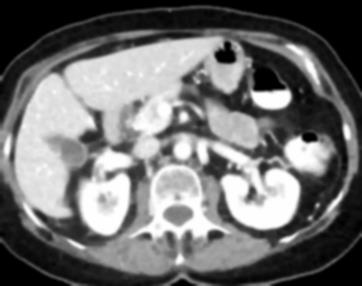

Due to the constraints of the imaging device and high cost in operation time, computer tomography (CT) scans are usually acquired with low intra-slice resolution. Improving the intra-slice resolution is beneficial to the disease diagnosis for both human experts and computer-aided systems. To this end, this paper builds a novel medical slice synthesis to increase the between-slice resolution. Considering that the ground-truth intermediate medical slices are always absent in clinical practice, we introduce the incremental cross-view mutual distillation strategy to accomplish this task in the self-supervised learning manner. Specifically, we model this problem from three different views: slice-wise interpolation from axial view and pixel-wise interpolation from coronal and sagittal views. Under this circumstance, the models learned from different views can distill valuable knowledge to guide the learning processes of each other. We can repeat this process to make the models synthesize intermediate slice data with increasing inter-slice resolution. To demonstrate the effectiveness of the proposed approach, we conduct comprehensive experiments on a large-scale CT dataset. Quantitative and qualitative comparison results show that our method outperforms state-of-the-art algorithms by clear margins.

翻译:由于成像装置的限制和操作时间成本高,计算机断层扫描通常以低切片分辨率获得。改进切片内分解法有利于人类专家和计算机辅助系统进行疾病诊断。为此,本文件制作了新的医疗切片合成法,以增加解片之间的解析。考虑到临床实践中总是没有地面真相中间医疗切片,我们采用渐进的跨视图相互蒸馏战略,以自我监督的学习方式完成这项任务。具体地说,我们用三种不同的观点来模拟这一问题:从轴视中切片间解法和从正弦和方位角度对等离子间解法。在此情况下,从不同观点中学习的模型可以提取宝贵的知识,用以指导彼此的学习过程。我们可以重复这一过程,使模型合成中间切片数据,同时增加分裂分辨率。为了证明拟议方法的有效性,我们在大规模CT数据集上进行了全面的实验。通过清晰的定量和定性的算法比较结果显示,我们的方法将超越了一种方法。